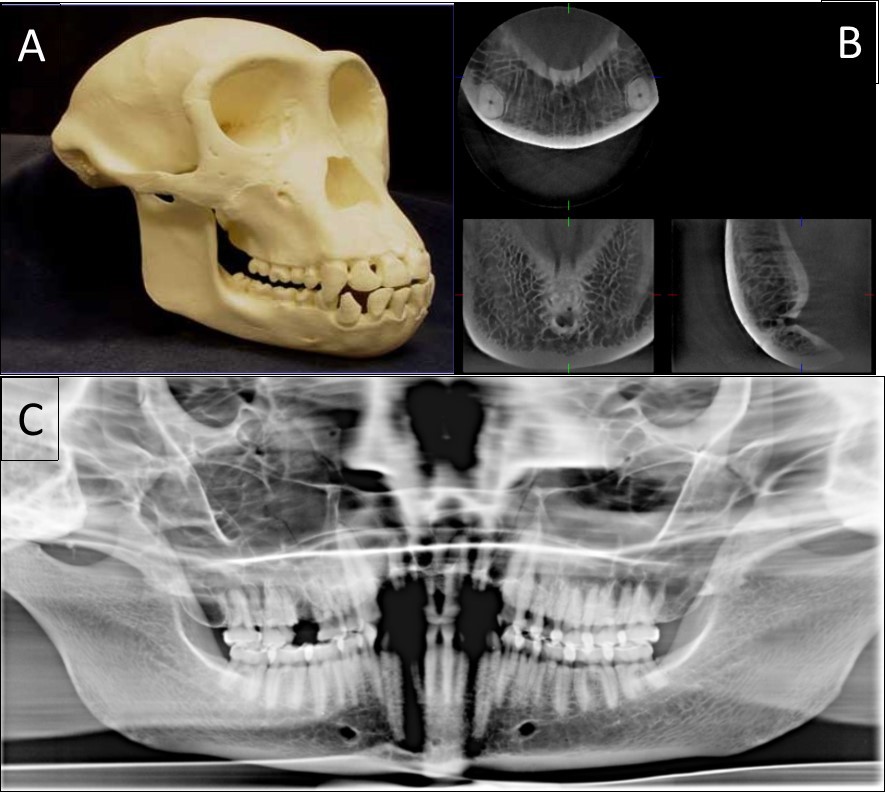

The typical images from modern human and great apes with different anatomical features were shown in Figure 1 and Figure 2. A group of variables were categorized as: the presence of the incisive canal, the number of mandibular canal bifurcations, the potential occurrence of an anterior loop, the presence of the incisive canals, its end-point and connection of the incisive to the lingual canals (Figure 3). Interspecific variability was determined by comparing contemporary human and great ape mandibles. In this analysis, mandibles from the different geographical locations were grouped in the human group, and then compared to mandibles of chimpanzees and gorillas.

Figure 1.The classical sample images with different anatomical features. A general view of a 20-year-old chimpanzee (A), its three-dimensional CBCT view (B) and two-dimensional panoramic view (C).